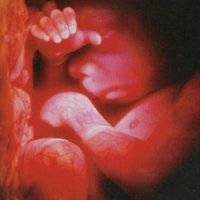

Малюк в 23 тиждень вагітності

Розвиток плода на 23 тижні вагітності

У цей період малюк активно росте і починає набирати вагу. Дитина на 23 тижні вагітності важить близько 500 грам, а зростання його становить близько 30 см. У цей період закінчується оформлення мозочка і середнього відділу головного мозку. Цей орган важить близько 100 грам. Триває нервово-психічний розвиток плода.

На цьому тижні активно розвиваються дихальні органи малюка. Ще не сформовані легені починають здійснювати дихальні рухи, таким чином тренуються дихальні м'язи малюка і розвивається грудна клітка. Так само в легких починають формуватися альвеоли, які активно виробляють сурфактант - речовина, необхідне для нормального функціонування легенів після народження. Невелика кількість навколоплідних вод під час дихальних рухів потрапляє в грудну клітку малюка, якась кількість розсмоктується, частина виштовхується назовні. Такі дихальні вправи здійснюються під керівництвом дихального центру в головному мозку.

Всі внутрішні органи плода активно працюють: функціонує печінка, відкладаючи запаси глікогену, селезінка і відсталий мозок займаються кроветворением. У цей період закладається імунітет малюка. Над цим активно працює вилочкова залоза і лімфатичні вузли. Кількість лімфоцитів ще не достатня, щоб самостійно протистояти інфекціям, цю функцію виконують антитіла матері.

До шостого місяця свого внутрішньоутробного розвитку, малюк вже вміє ковтати, смоктати, легені починають тренуватися «дихати», поступово малюк набуває основні життєві навички. Травна система ще остаточно не сформована, але, тим не менш, дитина заковтує близько півлітра амніотичної рідини протягом дня. Рідка частина виводиться з організму з сечею, що говорить про достатню зрілість нирок.

На 23 тижні вагітності місця в животі мами для дитини досить, він постійно перекидається і змінює своє положення, його рухи стають більш активними і відчутними. Саме тому в цей період лікар призначається другий планове УЗД, на виявлення вад розвитку плоду. Якщо не зробити його вчасно, то інформативність цього виду дослідження різко знижується.